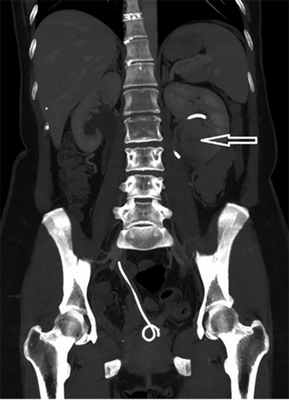

15.05.2019 госпитализирована с жалобами на истечение мочи через влагалище. При обследовании, по данным МСКТ брюшной полости (рис. 1), выявлены острый левосторонний пиелонефрит, абсцесс нижнего полюса левой почки, пузырно-влагалищный свищ, микроцистис, каликоэктазия справа, миграция мочеточникового стента справа.

Рис. 1. МСКТ-картина органов брюшной полости (завиток стента выполняет всю полость мочевого пузыря). Абсцесс нижнего полюса левой почки указан стрелкой.